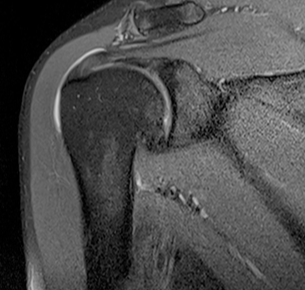

정상

회전근개파열

MRI 촬영시 정상적인 어깨의 경우 회전근개가 까맣게 나타나지만, 파열된 경우 하얗게 보여짐

2022.06.15

2022.06.17